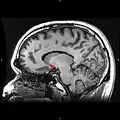

Sagittal MRI slice with highlighting (red) indicating the nucleus accumbens -